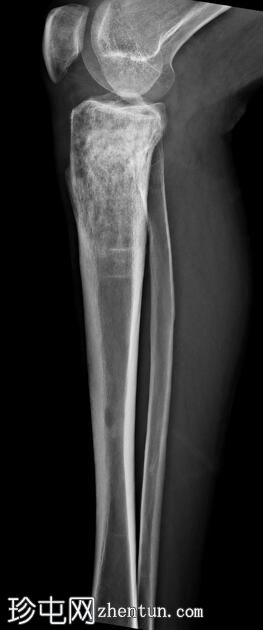

X线片

1.jpeg

正位片

右胫骨上三分之一骨骺及干骺端可见混合性溶骨-硬化性病变,部分区域呈浸润性改变,并可见较宽的过渡带。

未见皮质破坏或骨膜反应。